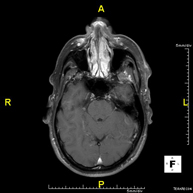

- Brain MRI (cranial)

This non-invasive diagnostic procedure uses an electromagnetic field and radio waves (from a transmitter and receiver) to acquire high-definition anatomical images of the brain. It is a radiation-free procedure. Indicated for: vascular problems, memory loss, epilepsy, headache, malformations, suspected tumour, meningitis.